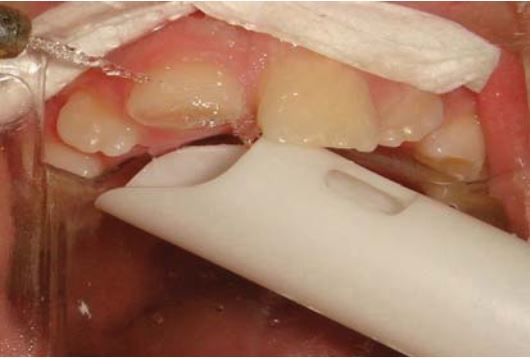

Cả răng cửa và mảnh gãy được khử trùng bằng Chlorhexidine 0.2% trước khi etching và bonding (H18.6 đến 18.11).

Bơm một lớp composite lỏng lên bề mặt răng hoặc bề mặt mảnh gãy để giúp tăng lưu giữ. Sau khi gắn lại mảnh gãy đúng vị trí thì sử dụng dụng cụ để loại bỏ composite thừa (H18.12).